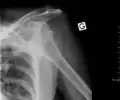

| Anterior dislocation of the left shoulder. | |

An anterior dislocation of the shoulder

Anterior dislocation of the right shoulder. AP X ray